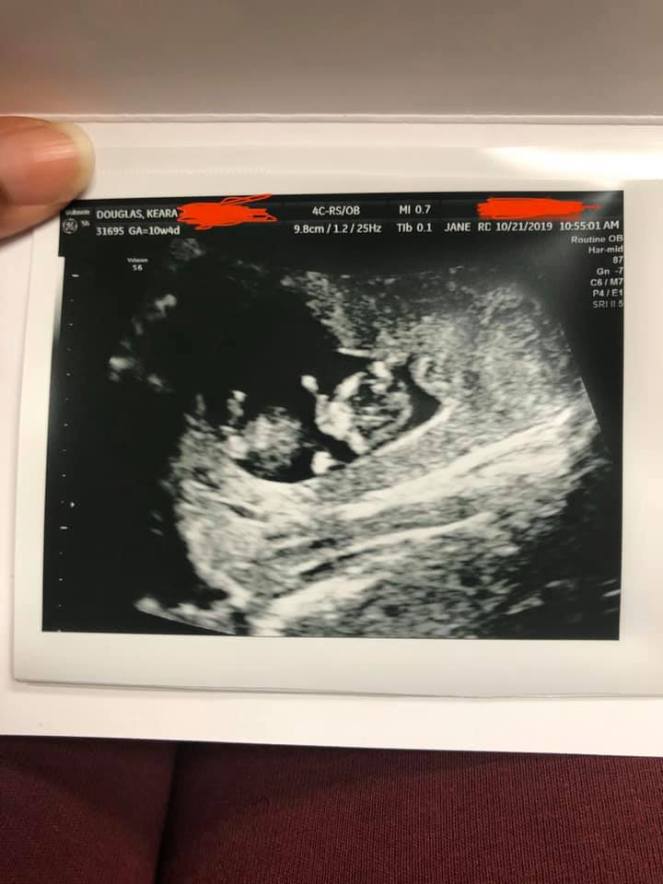

I know I just ran down the bad parts of my first trimester and I know you are probably thinking like damn were there any good parts Keara? Yes, there were. With me going into the bad parts of my pregnancy this is not to discourage anyone wanting to become pregnant nor is it to say that yours will turn out the same, it’s just a reflection of my experience. First off, the moment I found out I was pregnant I was excited completely. This is my first pregnancy so to know that I am currently carrying a whole human being is overwhelmly a happy feeling. I only wanted to talk about my unborn baby. Everything I done was centered around him/her including creating this blog segment. That first time seeing my baby for my first ultrasound appointment was the most magical and emotional experience ever. That confirmed everything and just made me want to do better as a person overall. I had a nasty smoking habit and had a drink socially from time to time beforehand, which this stopped both of those activities completely. I had already wanted to stop smoking so this was the push I truly needed to make that happen. I wanted to gain more healthy weight and of course my eating increased to make that happen. I wanted to focus on my goals and making more money and of course this was an additional push to make that happen. God truly worked in a mysterious way for me when it came to my goals for 2019 through me becoming pregnant for the first time.